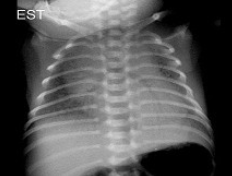

265、单项选择题

早产儿,男,生后6小时,于生后2小时出现呼吸困难,如图,最可能的诊断为()

A.新生儿肺炎

B.新生儿湿肺

C.新生儿肺出血

D.新生儿呼吸窘迫综合症

E.胎粪吸入综合征